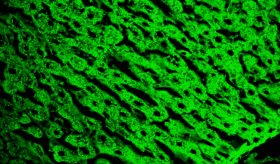

Estudios recientes han revelado la importancia de esta comunidad microbiana en la regulación del sistema inmunológico y la promoción de una barrera cutánea saludable.